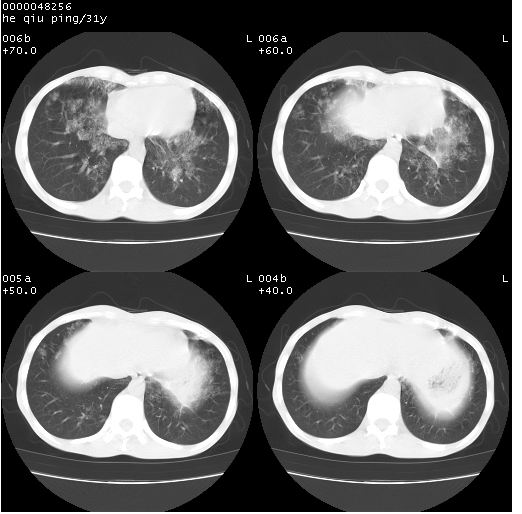

标题: CT13402:M,31Y。肺结核伴空洞形成?

咳嗽半月余,消瘦体质,呼吸音弱。无其他病史。cr:肺转移瘤待。

双上肺多发空洞,双飞散在分布大小不一的片状结高密度影节状大片状高密度影。符合结合肉芽肿形成及空洞形成。

双侧弥漫性病变,双上叶尖后段、下叶北段见多个空洞,多见于结核感染。右中叶及双下叶斑片状,结节状影,考虑为肉芽肿形成及支气管播散。但由于患者消瘦体质,抵抗力低下,若继发感染,如金葡菌肺炎也有可能。

应该是比较典型肺结核伴空洞形成,下肺野播散。

考虑为:两肺结核伴多发空洞形成、支气管播散。

结核空洞并播散,玫瑰花簇征。